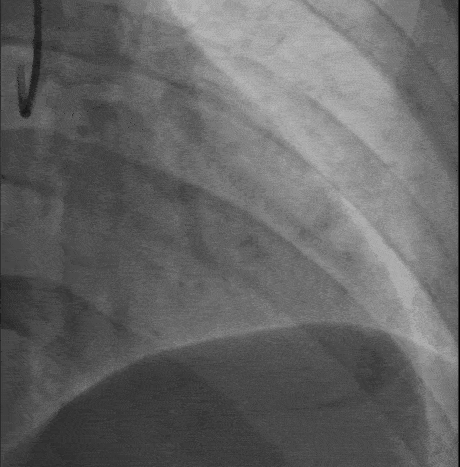

操作过程 XT-R顺利通过第一闭塞段

第二段病变通过困难角度过大更换XT-A仍通过失败 交换双腔微导管+Gaia-2

Gaia-2进入内膜下微调进入真腔交换工作导丝进行IVUS检查

DEB bingo 2.5*30mm 10atm 结果满意

IVUS-3